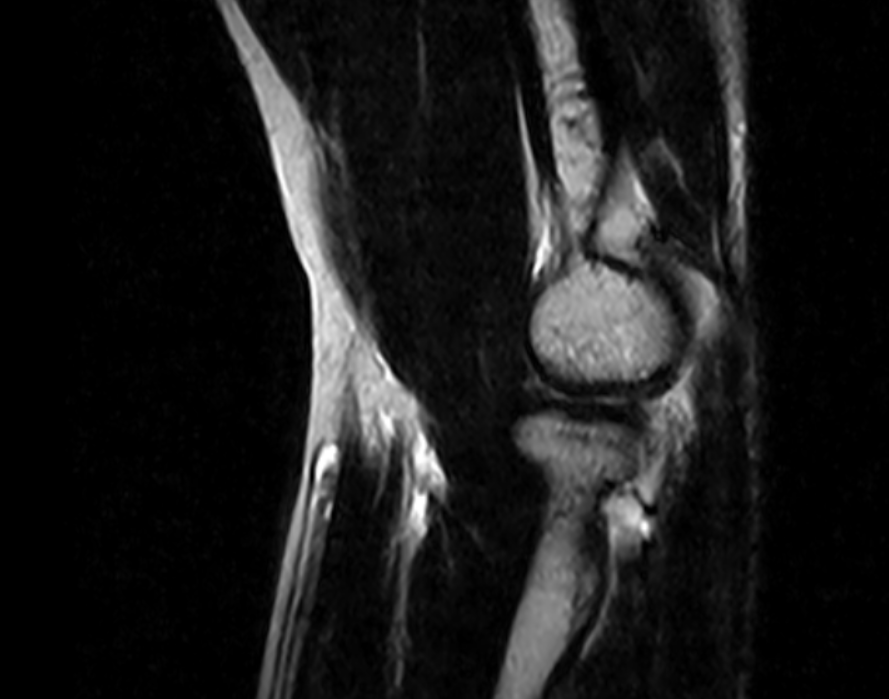

Imágenes Clínicas

El S-scan permite resonancias magnéticas cerebrales gracias a su amplia gama de aplicaciones a través de bobinas dedicadas.